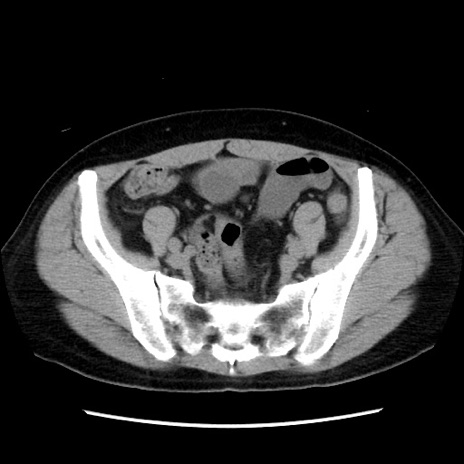

症例10(横断像)

【症例】 50歳代女性

【主訴】 腹痛

【現病歴】前日生レバーを食べた。今朝に排便あり。 昼前に突然発症の腹痛を生じ、当院救急外来を受診した。

【身体所見】 意識清明、腹部:平坦、軟、下腹部やや左を中心に圧痛・反跳痛あり、筋性防御あり

【データ】WBC 7800、CRP 0.07